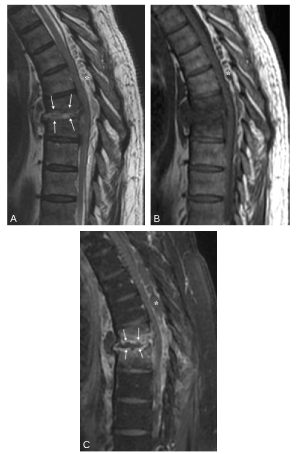

Fig. 52.3. Spondylodiscite infectieuse T7-T8 (cause extradurale).

IRM en coupes sagittales pondérées en T2 (A) et en T1, sans (B) et avec injection de gadolinium et saturation des graisses (C). Atteinte centrée sur le disque T7-T8 (flèches) qui apparaît en hypersignal en T2 et qui prend le contraste en périphérie. Cette atteinte s’étend aux corps vertébraux adjacents dont les plateaux sont irréguliers et aux espaces pré- et paravertébraux. Il existe également une coulée infectieuse épidurale postérieure (∗).

Source : CERF, CNEBMN, 2022.